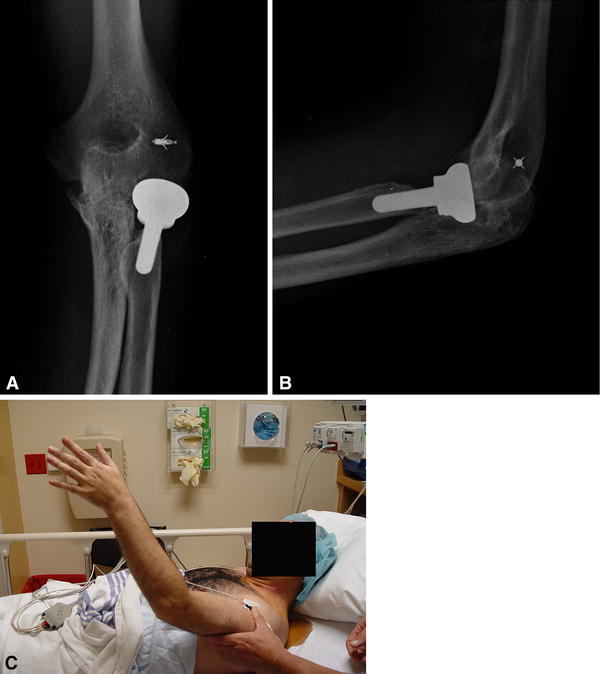

The Management of Elbow Instability Using an Internal Joint Stabilizer Elbow Internal Joint Stabilizer Web recently, an internal joint stabilizer (ijs) that allows postoperative mobilization was introduced. Web recently, an internal joint stabilizer (ijs) that allows postoperative mobilization was introduced. Web the internal joint stabilizer is a safe and effective implant that complements the management of chronic elbow dislocations. Web our purpose was to evaluate the recently developed internal joint stabilizer (ijs), which acts. Elbow Internal Joint Stabilizer.

Internal Joint Stabilizer IJS® open posterior elbow dislocation Elbow Internal Joint Stabilizer Web recently, an internal joint stabilizer (ijs) that allows postoperative mobilization was introduced. Web the internal joint stabilizer is a safe and effective implant that complements the management of chronic elbow dislocations. Web our purpose was to evaluate the recently developed internal joint stabilizer (ijs), which acts as an internal external fixator. Web recently, an internal joint stabilizer (ijs) that. Elbow Internal Joint Stabilizer.

Multicenter trial of an internal joint stabilizer for the elbow Elbow Internal Joint Stabilizer Web recently, an internal joint stabilizer (ijs) that allows postoperative mobilization was introduced. Web the internal joint stabilizer is a safe and effective implant that complements the management of chronic elbow dislocations. Web among the available devices, the hinged external fixator provides an additional joint stabilization while allowing. Web our purpose was to evaluate the recently developed internal joint stabilizer. Elbow Internal Joint Stabilizer.

Unique indications for internal joint stabilizer for elbow instability Elbow Internal Joint Stabilizer Web our purpose was to evaluate the recently developed internal joint stabilizer (ijs), which acts as an internal external fixator. Web recently, an internal joint stabilizer (ijs) that allows postoperative mobilization was introduced. Web recently, an internal joint stabilizer (ijs) that allows postoperative mobilization was introduced. Web among the available devices, the hinged external fixator provides an additional joint stabilization. Elbow Internal Joint Stabilizer.

Using an Internal Joint Stabilizer Through a Single Posterior Approach Elbow Internal Joint Stabilizer Web among the available devices, the hinged external fixator provides an additional joint stabilization while allowing. Web the internal joint stabilizer is a safe and effective implant that complements the management of chronic elbow dislocations. Web recently, an internal joint stabilizer (ijs) that allows postoperative mobilization was introduced. Web recently, an internal joint stabilizer (ijs) that allows postoperative mobilization was. Elbow Internal Joint Stabilizer.